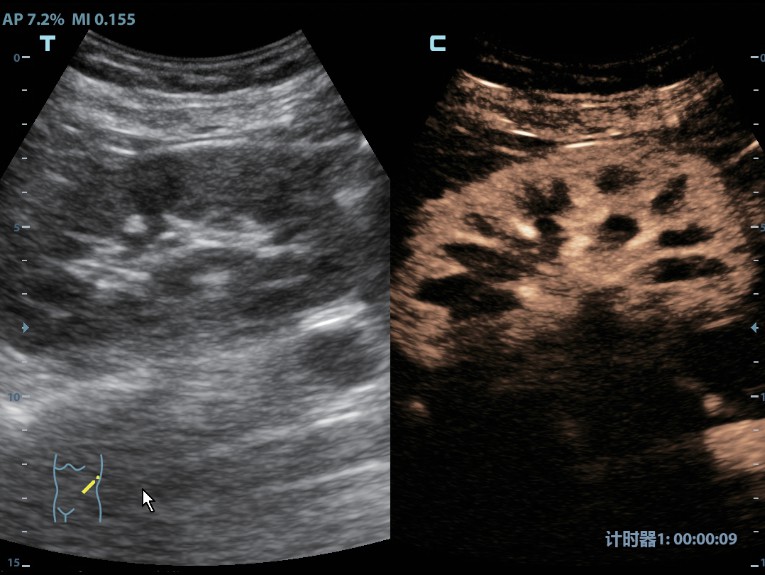

Клинические изображения